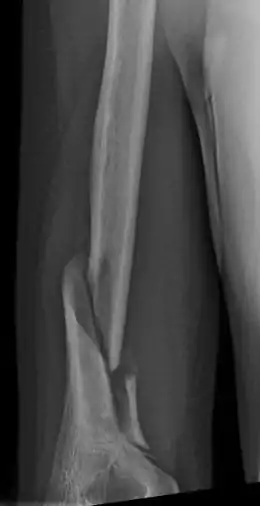

Holstein–Lewis fracture

A Holstein–Lewis fracture is a fracture of the distal third of the humerus resulting in entrapment of the radial nerve.

| Holstein–Lewis fracture at 5 weeks post fracture | |